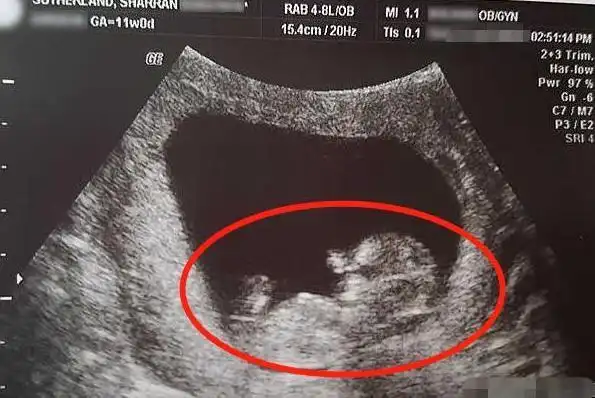

新愿景!怀孕14周胎儿彩超图"送子天下"-第2张图片-华泰博客

其它 典型病例(胎儿腹裂) 写美篇【病例简介】孕14周,胎儿腹壁脐带

宝妈怀孕14周意外流产,"胎儿"模样曝光!才10厘米但手脚已成形

幼儿教育 育儿理论经验 胎儿发育过程图之第十四周发育过程图 孕14周

【怀孕14周】怀孕十四周胎儿图,怀孕14周吃什么,注意什么_亲子百科